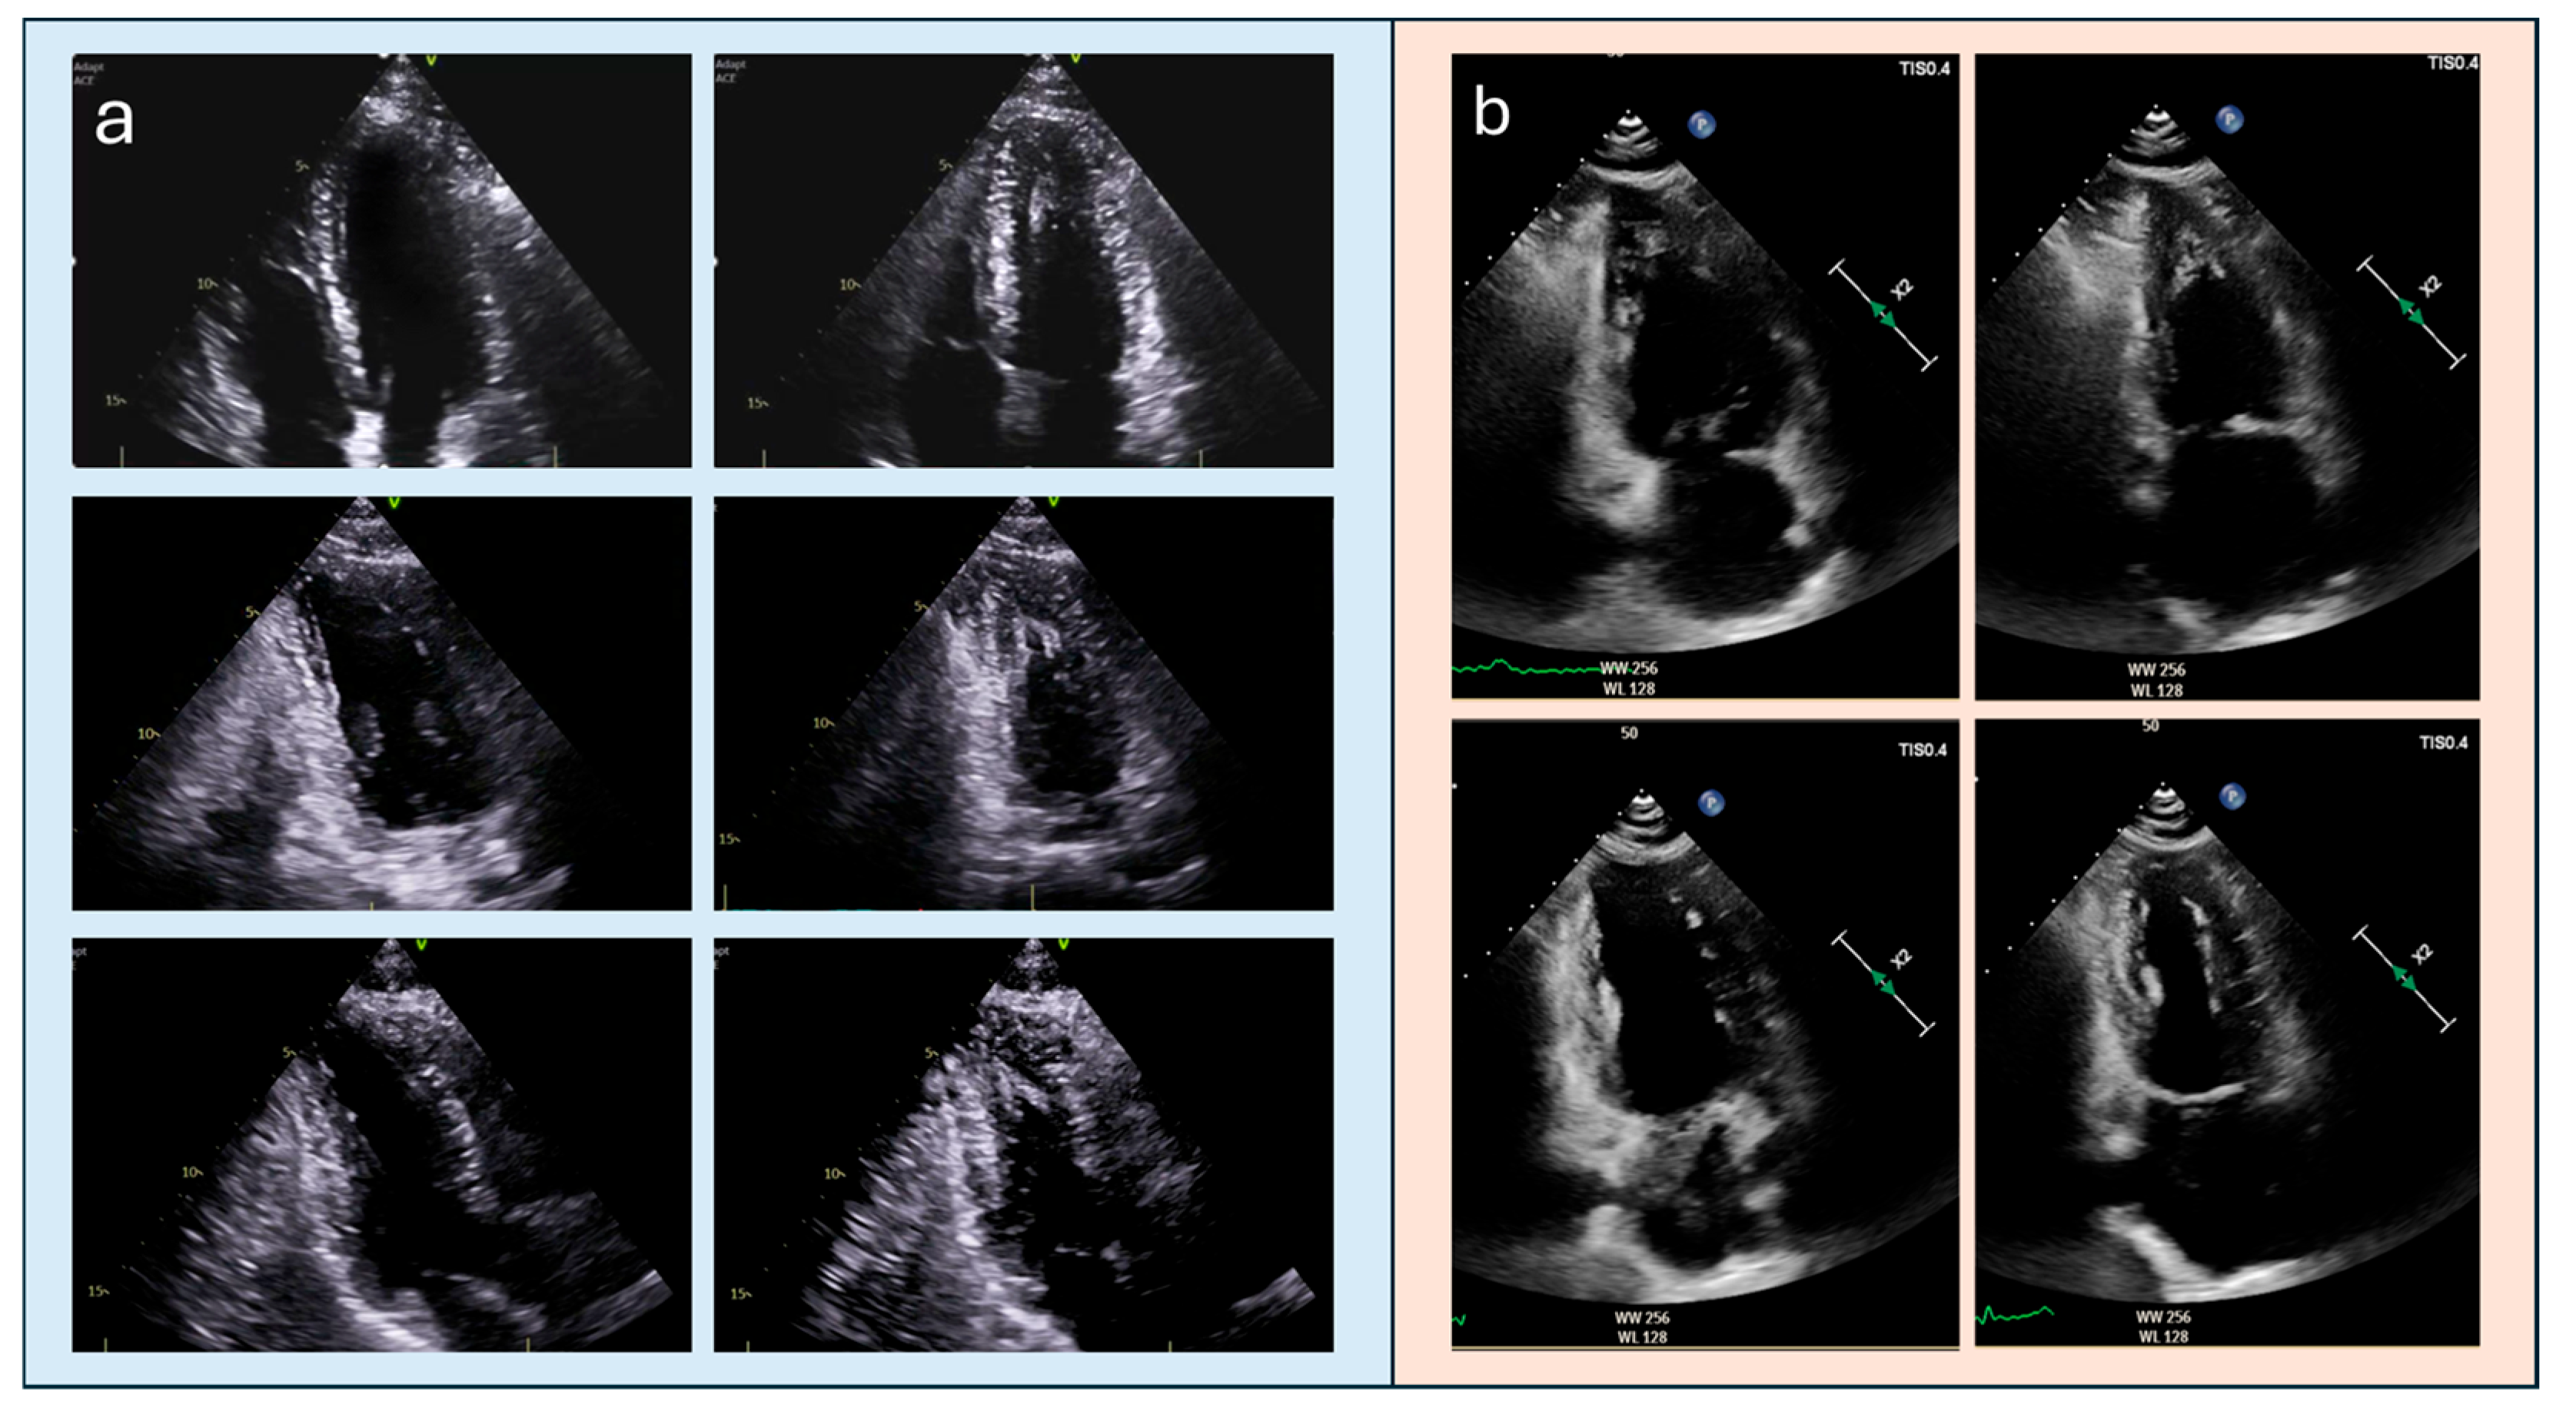

4.2. Apical Obliteration